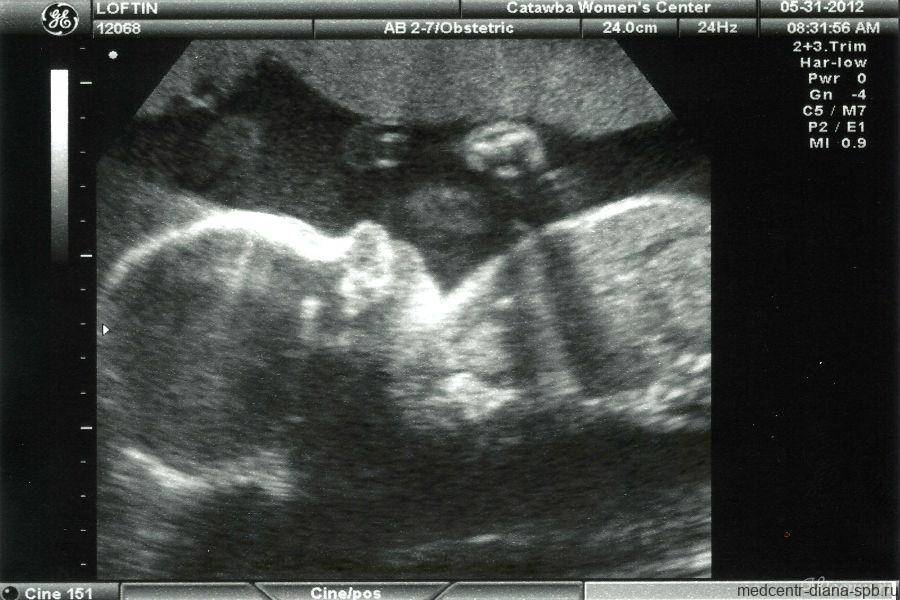

УЗИ

На 22-й неделе в редких случаях возможно проведение второго скрининга (УЗИ) для выявления возможных патологий у плода. Во время исследования специалист оценит не только состояние будущего малыша и соответствие его параметров сроку, но и изучит матку, плаценту и пуповину. При выявлении отклонений от нормы возможно назначение дополнительных инвазивных методов исследований.